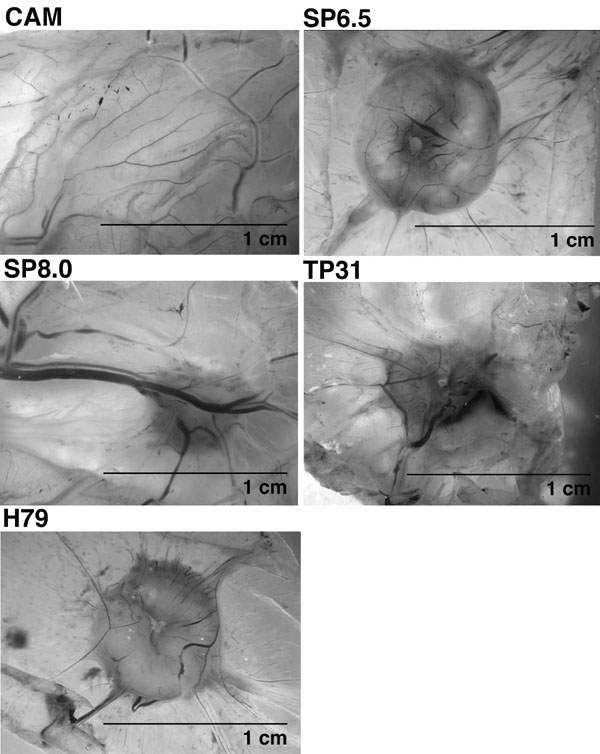

Figure 3. In vivo chick embryo chorioallantoic membrane (CAM) tumor assay

Representative macroscopic views show tumors obtained from the inoculation of SP6.5, TP31, SP8.0, and H79 uveal melanoma cell lines on the CAM of chick embryos. CAM represents control without inoculation. The scale bar represents 1 cm.